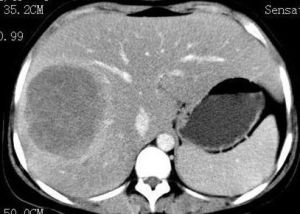

1.糖原累積症Ⅲ型體檢檢查本身難與GSD-Ⅰ型區別。嬰兒期肝腫大、發育障礙較突出,部分患兒在4~6歲時可出現脾腫大,此患兒可有肝纖維化的證據,但不一定發展為肝硬化和肝功能衰竭。

嬰兒出生後幾個月多無症狀,一歲內症狀隱匿,但最早出現症狀可在3個月時,最晚是15個月。可有一些非特異性消化道症狀,肝、脾腫大,肝功能不全生長遲緩等症狀和體徵,肌肉張力低、萎縮。隨病情發展可有腹壁 靜脈曲張 、肝硬化門脈高壓、腹水和食道靜脈曲張,該病診斷後存活期多為2~37個月,偶3~4年,最後多死於慢性肝功能不全、上 消化道出血 、心力衰竭、感染。